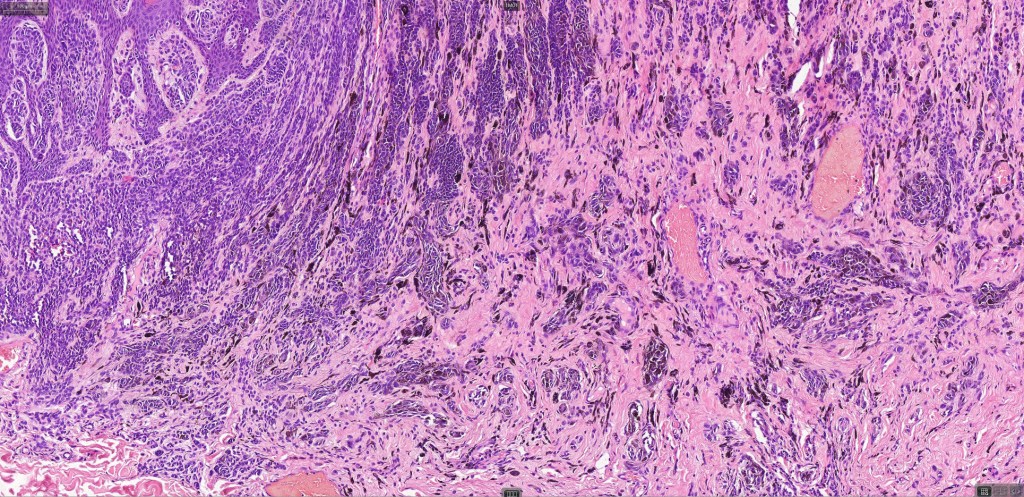

This is uncommon and presents clinically with a history of recent change in color of a common or less often congenital nevus causing concern for melanoma by the clinician. Some, but not all are probably deep penetrating and combined nevus variants. Others may represent follicular type-A cell nests. It is characterized by the presence of deep nest(s) of type -A nevus cells surrounded by & with overlying type-B nevus cells.